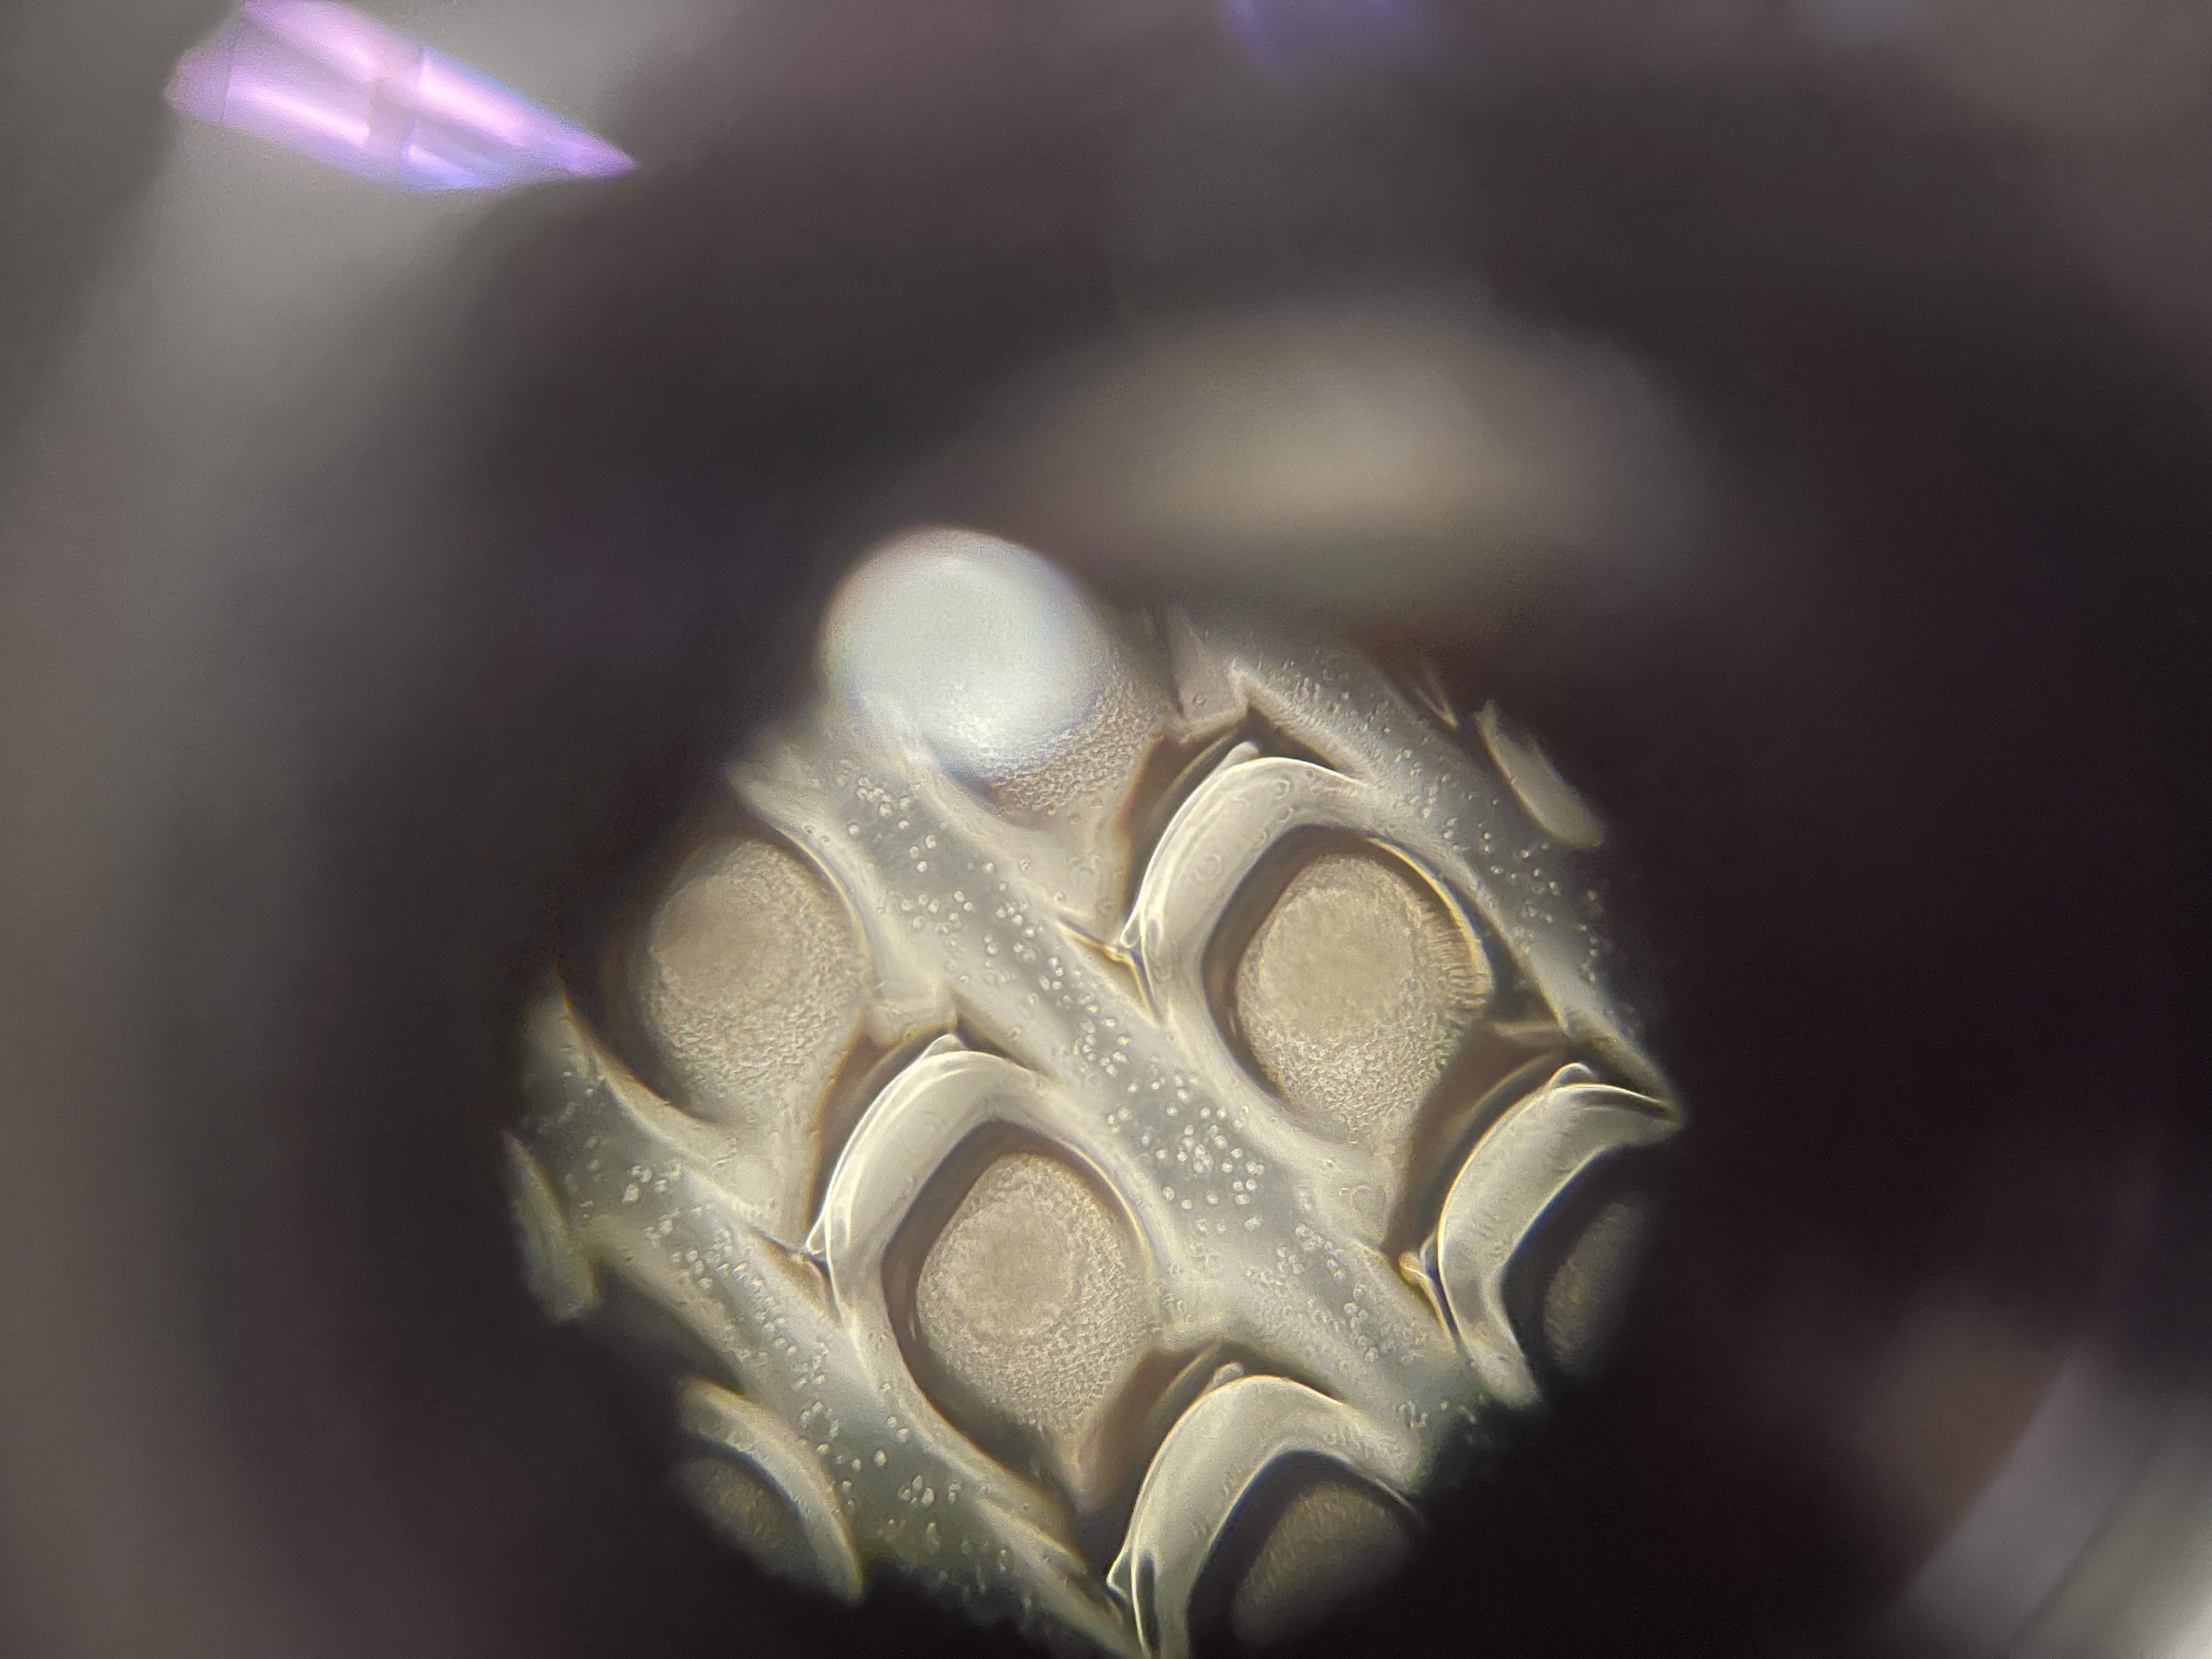

Cultivated retinal organoids from embryonic pluripotent stem cells (EPSCs), guiding differentiation through a staged protocol toward retinal progenitor and photoreceptor cell fates. The work involved maintaining organoid sheets in culture, optimizing media formulations and timing for each differentiation stage, and characterizing the resulting tissue by morphology and marker expression. The goal was to produce tissue that could serve as a testbed for implant interaction studies and eventually as transplantable material for degenerative retinal disease.

Retinal organoid

Embryonic cell aggregations in culture/figcaption>